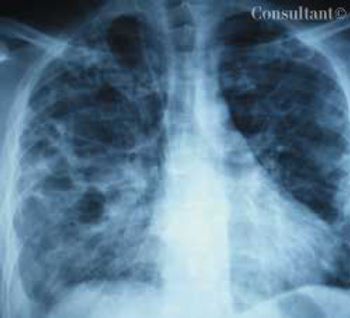

A 33-year-old man with AIDS presented to the emergency department with fever, dyspnea, cough, and pleuritic chest pain of 3 days' duration. He had had a Pneumocystis carinii infection 3 years before recently emigrating from the Dominican Republic to the United States. Promiscuous sexual activity was his only risk factor for HIV infection. The patient did not take antiretroviral medications or protease inhibitors because of their cost.

Severe shortness of breath, a dry cough, and a 10-day history of fever sent a 37-year-old man with HIV disease to the emergency department. He complained of a poor appetite and had lost 10 lb over the last 10 days.

A 33-year-old man with AIDS presented to the emergency department with fever, dyspnea, cough, and pleuritic chest pain of 3 days’ duration. He had had a Pneumocystis carinii infection 3 years before recently emigrating from the Dominican Republic to the United States.